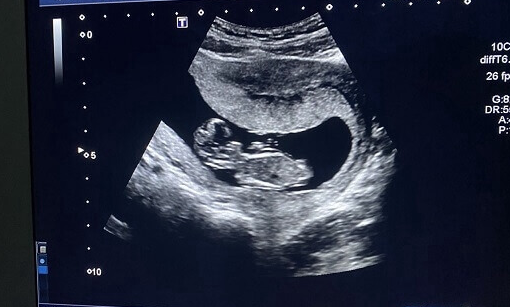

导读: 在孕期,确保胎儿获得充足的氧气对胎儿的健康发育至关重要。以下为孕妇们介绍几种增加胎儿氧气的有效方法,其中适当多走动好处多多。

在孕期,确保胎儿获得充足的氧气对胎儿的健康发育至关重要。以下为孕妇们介绍几种增加胎儿氧气的有效方法,其中适当多走动好处多多。